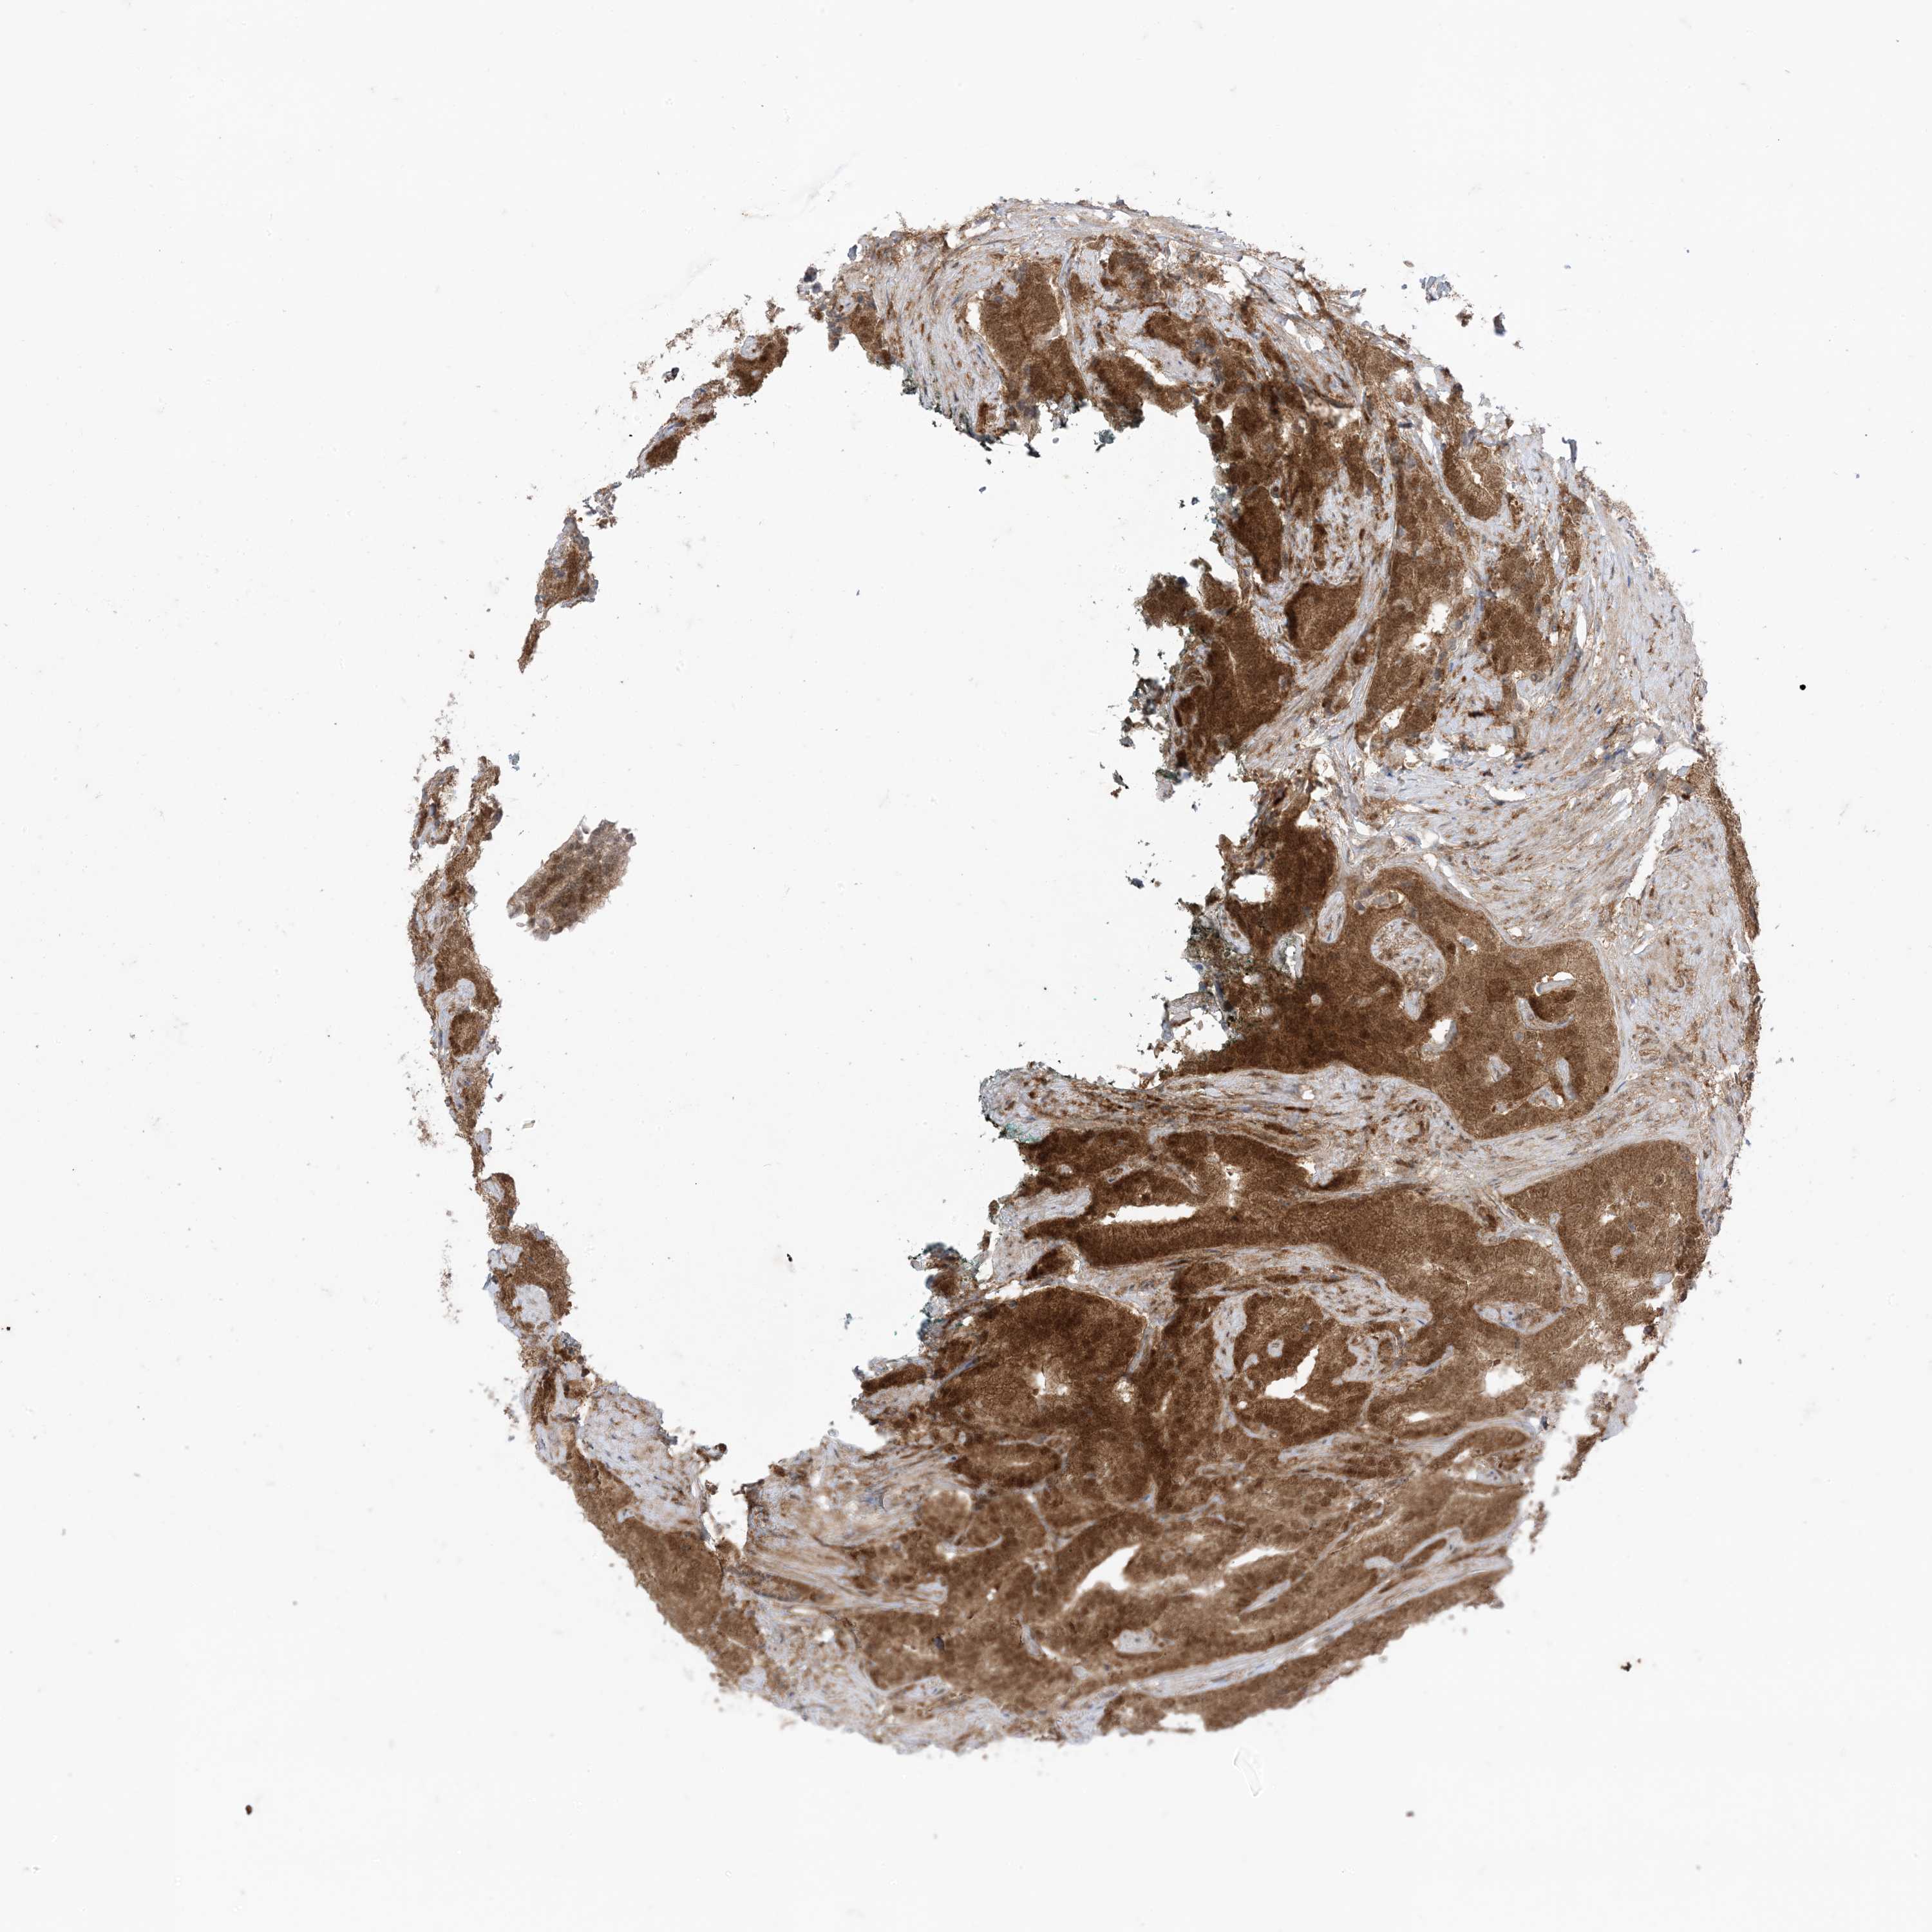

PROSTATE CANCER - Protein expressioni

A mouse-over function shows sample information and annotation data. Click on an image to view it in a full screen mode. Samples can be filtered based on level of antibody staining by selecting one or several of the following categories: high, medium, low and not detected. The assay and annotation is described here.

Note that samples used for immunohistochemistry by the Human Protein Atlas do not correspond to samples in the TCGA dataset.

Antibody stainingi

Antibody staining in the annotated cell types in the current human tissue is reported as not detected, low, medium, or high, based on conventional immunohistochemistry profiling in selected tissues. This score is based on the combination of the staining intensity and fraction of stained cells.

Each image is clickable and will lead to virtual microscopy that enables deeper exploration of all samples and also displays staining intensity scores, fraction scores and subcellular localization as well as patient and tissue information for each sample.

HPA005695

CAB022068

CAB035999

CAB080052

CAB080054

CAB080098

Adenocarcinoma, Low grade

Adenocarcinoma, High grade

Adenocarcinoma, NOS

Adenocarcinoma, Medium grade